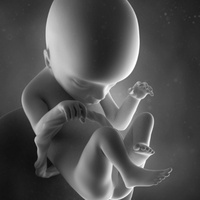

Мочевые органы и половые железы закладываются независимо друг от друга, но при дальнейшем развитии они формируют анатомически единую систему органов.Аномалии развития мочеполовых органов составляют более 30 % всех врожденных пороков развития.